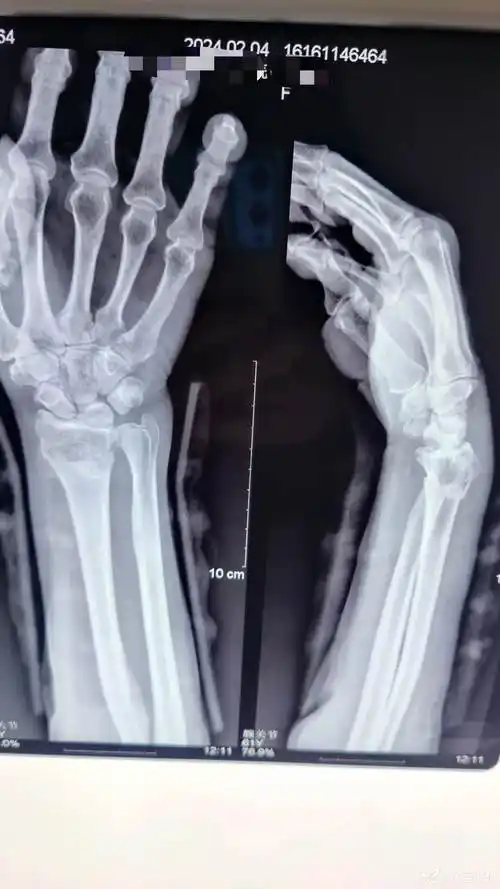

左陈旧性colles骨折一例